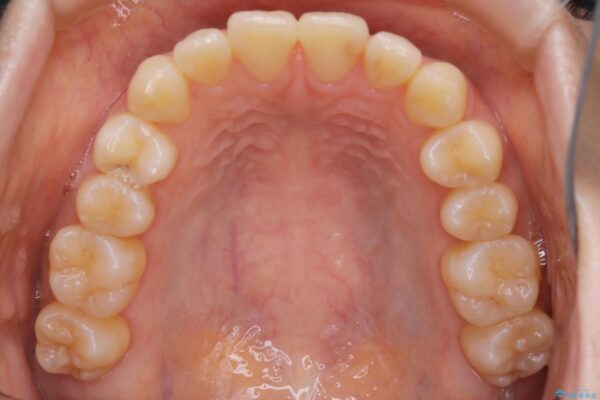

20代 女性 インビザラインで短期間矯正

- 20代女性

- 1年

- 49.5万円(インビザライン ライトパッケージ)

下の前歯のガタつきが気になるとご来院された患者様です。

インビザラインのライトパッケージにて、歯列拡大とディスキング(IPR)をを行いスペースをつくり非抜歯で治療を行いました。